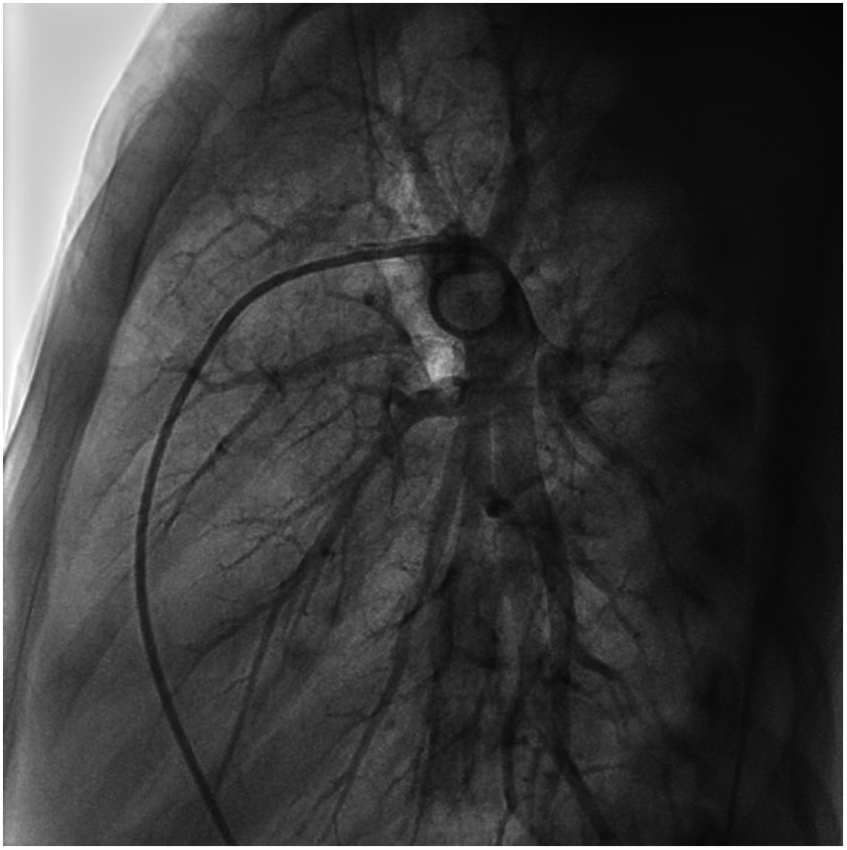

We performed a detailed evaluation of the cardiovascular system, including tests for right-to-left diverged heart disease, pulmonary arteriovenous fistula, severe valve regurgitation, and pulmonary hypertension.After conducting detailed echocardiography and cardiac CTA, we performed cardiac catheterization. The results of cardiac catheterization were negative. Cardiac catheterization findings are shown in Figures 3–6. We were unable to find a shunt at the atrial, ventricular, or aortic levels. The child's echocardiogram and cardiac macrovascular CT results were normal, ruling out complex congenital heart disease such as pulmonary atresia.

Figure 5

Frontal views of the child's right pulmonary arteriogram. No pulmonary arteriovenous fistula was found.